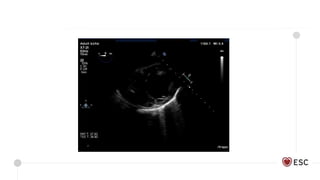

• Echo parameters superior in

determining successful vs non-

successful weaning

• Aotic VTI, TDSa and EF greatest

predictors – despite criticism in

literature regarding load-

dependence and questionable

measures of contractility

Int Care Med 2011

Echo parameters

Retrieval for VA ECMO for severe biventricular heart failure following

OOHCA

3.3 L VA ECMO Support

4 Chamber Longitudinal strain

= -14.7%

LVOT VTI = 13.6

3.0 L VA ECMO Support

4 Chamber Longitudinal

strain = -17.3%

LVOT VTI = 12.4

1.0 L VA ECMO Support

strain = -17.9%

LVOT VTI = 14

Dr Alessia Gambaro, with permission